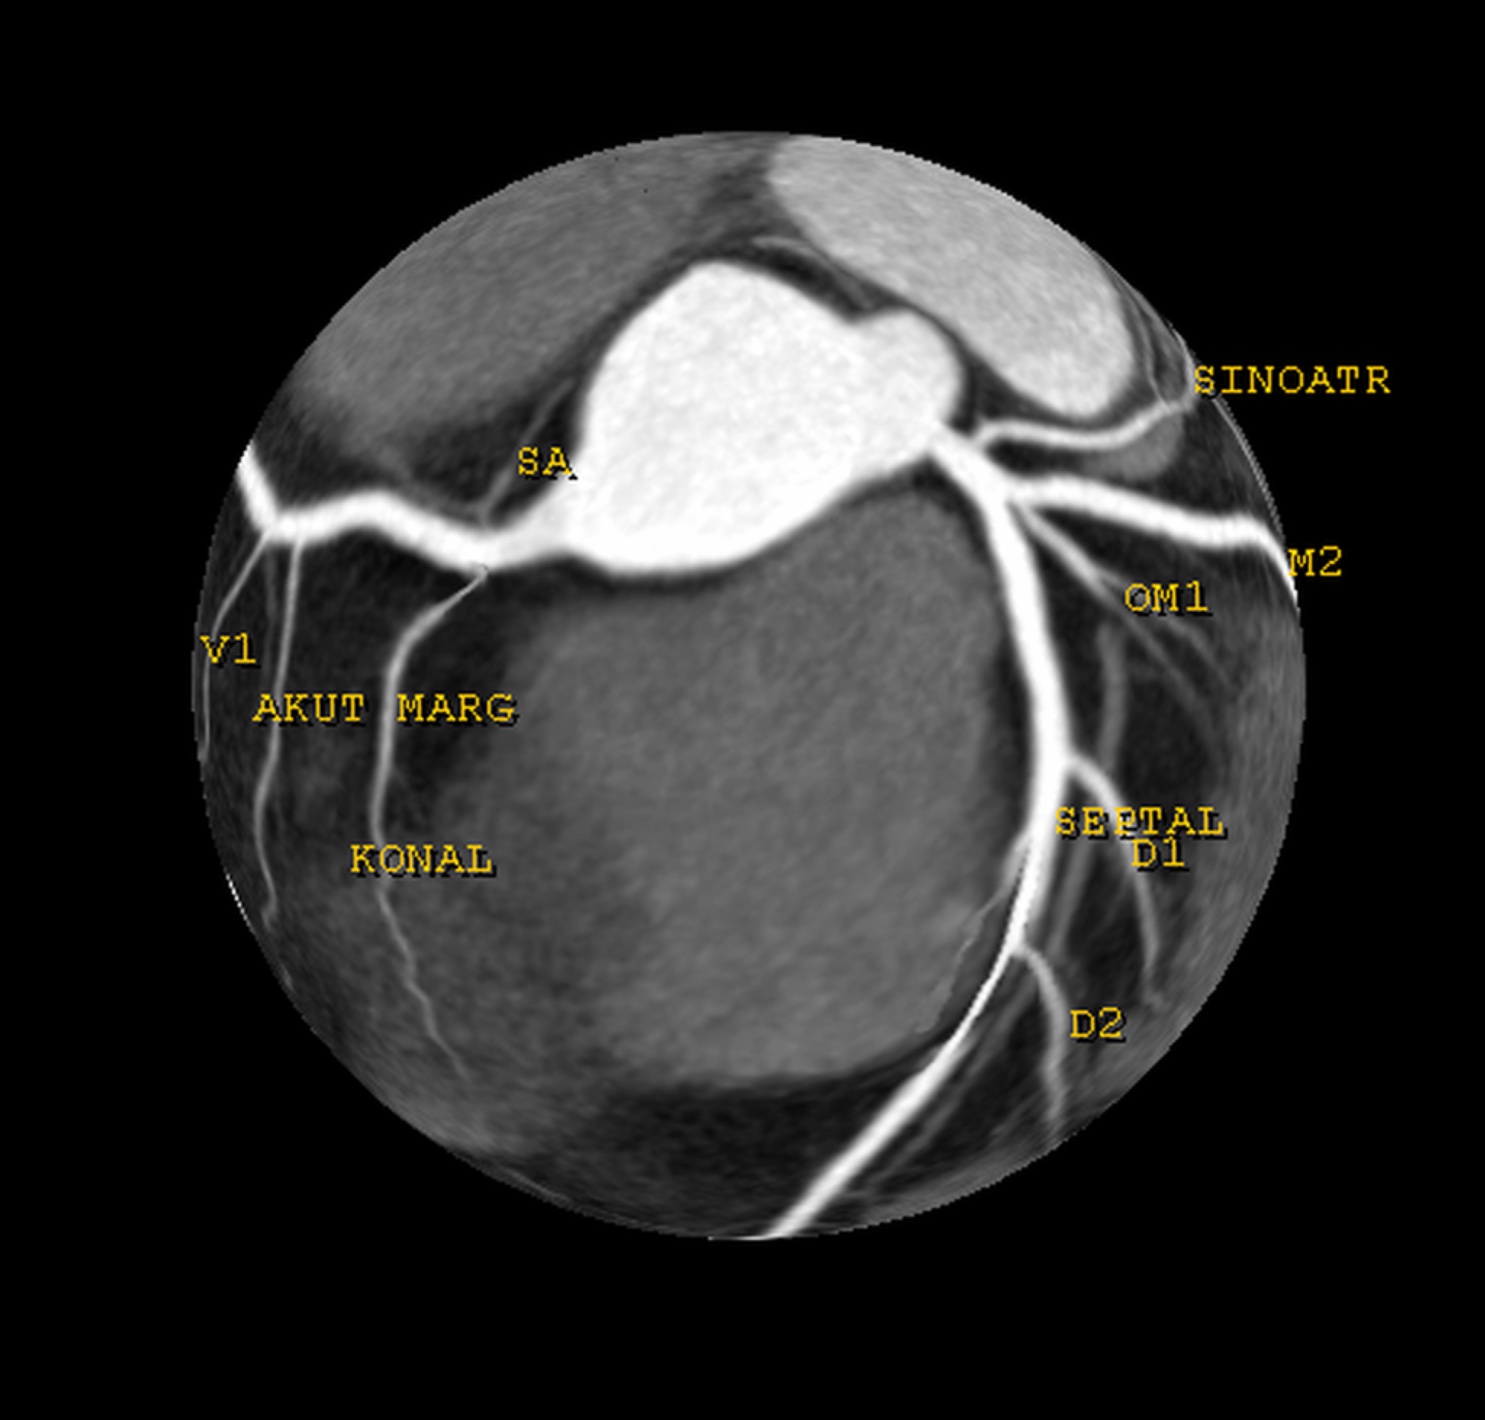

Sol kalp ventriküler anjiyografi, kalbin sol tarafındaki ana pompalama odası olan sol ventrikül ve bu odanın beslendiği koroner arterlerin görüntülenmesini sağlayan bir tıbbi görüntüleme testidir. Bu test genellikle kalp damar hastalıklarının tanısında kullanılır ve cerrahi müdahale gerektiren durumları belirleme amacı taşır.

Sol kalp ventriküler anjiyografi, bir hastaneye yatış gerektiren bir prosedürdür. Hasta, genellikle lokal anestezi veya hafif sedasyon altında olacaktır. İşlem sırasında, bir kateter (uzun ince bir tüp) kas içine yerleştirilir ve bu kateter, kontrast madde enjekte edilerek koroner arterlere yönlendirilir. X-ışınları kullanılarak alınan görüntüler, doktorlara kalbin durumu ve damarlarının tıkanıklıkları hakkında detaylı bilgi sağlar.

Sol kalp ventriküler anjiyografi sonuçları, doktorlar için değerli birer pusuladır. Damarsal tıkanıklıklar, plak birikimleri ve kan akışındaki bozukluklar bu görüntülerle tespit edilebilir. Tedavi planı, bu sonuçlara göre şekillenir ve hasta için en etkili tedavi yöntemleri belirlenir. Bu aşamada, hastaların tedavi süreci boyunca düzenli takip edilmesi de önemlidir.